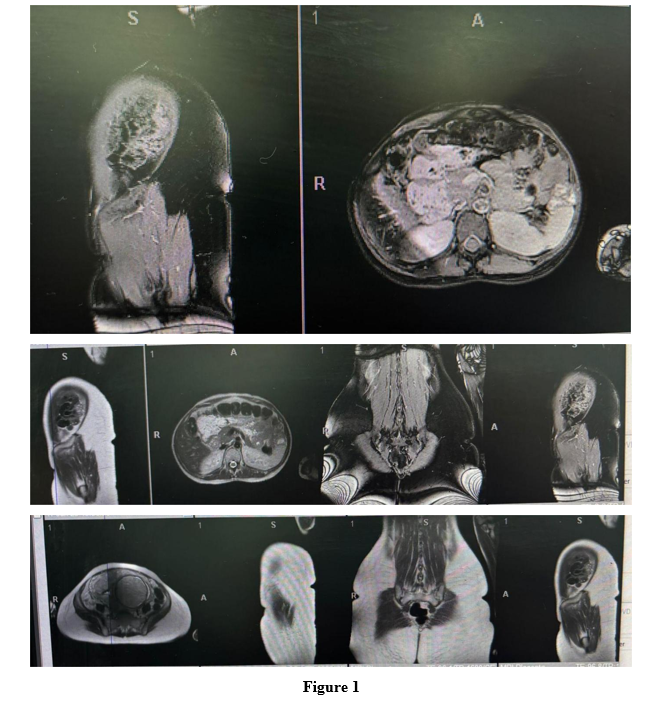

Bedside ultrasound confirmed a single viable fetus in cephalic presentation with placenta previa major. MRI was requested to assess for placenta accreta, but the report was pending at the time of intervention. Full blood count, liver/ renal profile and coagulation profile were normal. Group and save as well as cross-matching for four units was requested.

Figure 1